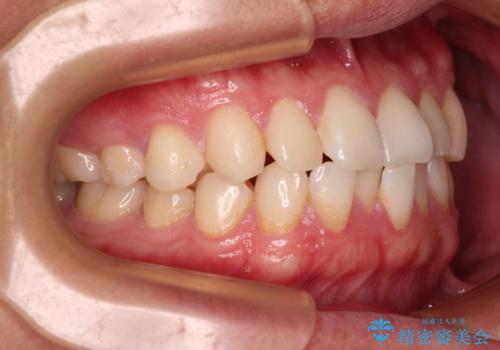

・上顎左右の第二大臼歯が頬側へ転移し、シザーズバイト(scissors bite)の状態

・上顎左側第二小臼歯が90度捻転しており、噛み合わせに影響

・奥歯のシザーズバイト改善には、口蓋側にアンカースクリュー(TAD)を設置し、矯正用ゴムで内側に牽引

・捻転した第二小臼歯は、ワイヤーと矯正用ゴムの力を用いて正しい位置へ回転移動

**前歯のデコボコ(叢生)**が整い、歯列全体が美しく改善

シザーズバイトの奥歯も正常なかみ合わせに改善

捻転歯も回転が修正され、全体的に清掃性・咀嚼効率が向上